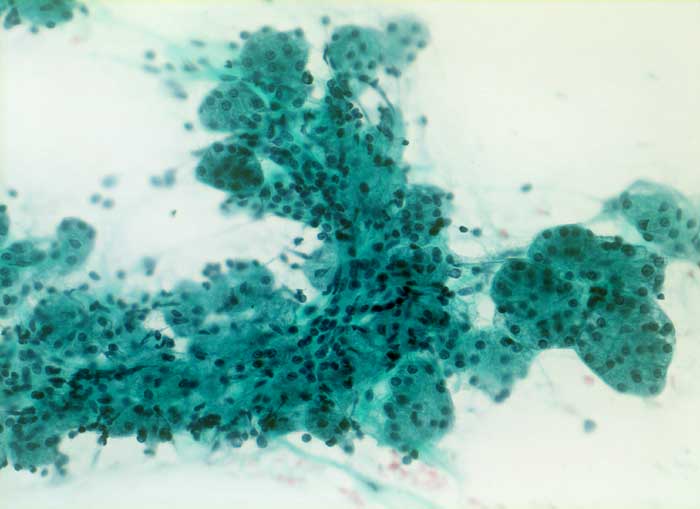

Akute Sialadenitis

Akute bakterielle Sialadenitiden werden oft verursacht durch eine Gangobstruktion (z.B. Steine), können aber auch bei schlechter Mundhygiene oder bei Immunsupression vorkommen. Die Feinnadelpunktion kann durch eine Druckverminderung zu einer Schmerzreduktion führen. Das Punktat gleicht einem Abszess mit neutrophilen Granulozyten, Fibrin und Nekrosen. Gelegentlich sind Erreger nachweisbar. Zu einem späteren Zeitpunkt kommen Lymphozyten, Plasmazellen, Makrophagen, Granulationsgewebe und Epithelien mit regenerativen Veränderung/Atypien zur Darstellung.